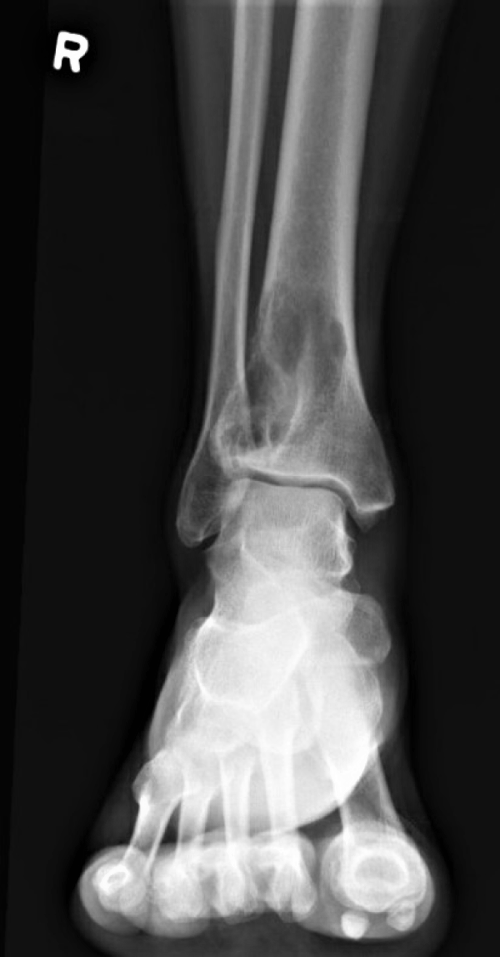

Radiographic film of the right ankle showed 5 cm eccentric lytic lesion involving the right distal tibia with features of cortical destruction and endosteal scalloping extending close to the articular surface (Figure 1). Nuclear medicine bone scan showed focal uptake in the known lytic lesion in the distal right tibia. The patient had an excisional biopsy to establish the diagnosis and subsequently had the mass excised with bone curettage.